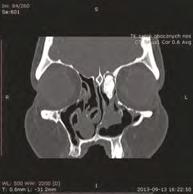

ykon je si j w trzech p aszczyznach:

strza kowej, czo owej, podstawnej w warstwach, co mm

omo ra ia komp terowa zatok przynosowych , po ktrym por sza si dzie chir r oka e patolo i , ezpieczne szlaki i czyhaj ce nie ezpiecze stwa np anomalie anatomiczne przypadk korzystania z nawi acji wska e np o raniczenie pola operacyjne o (patrz o razy p aszczyzn a, , c ryc ast pny, niez dny etap na ki to j zaj cia praktyczne na zw okach (o ecnie na specjalnych antomach

omo ra ia komp terowa zatok przynosowych w trzech p aszczyznach: A strza kowa, B czo owa, podstawna

A B